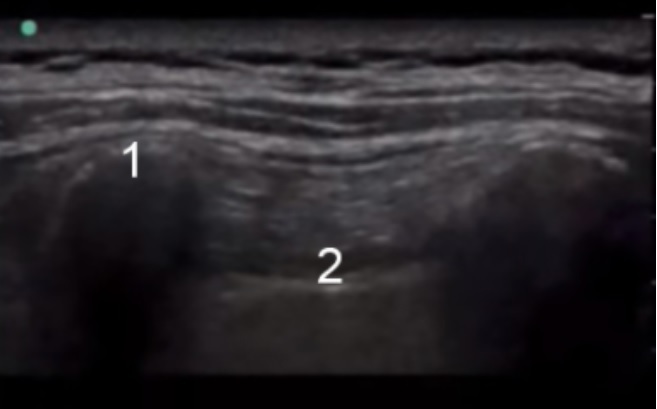

傍脊柱解剖1画像

横断プロセス

内肋間膜